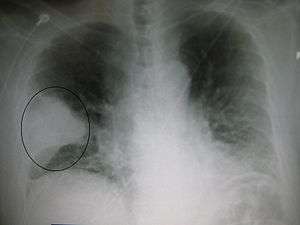

Right upper lobe pneumonia as marked by the circle.- Left upper lobe pneumonia with a small pleural effusion.

- Right lower lobe pneumonia as seen on a lateral CXR